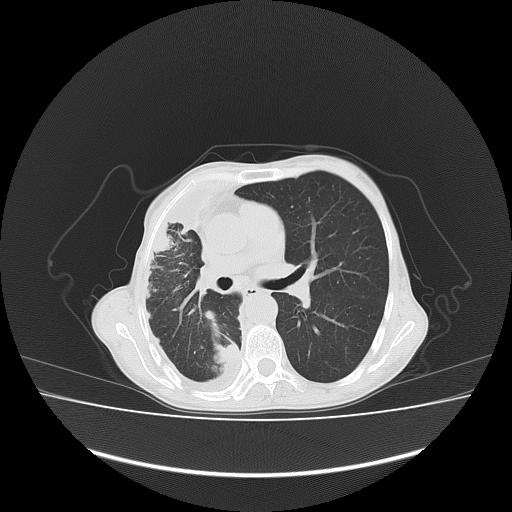

可见多发肺内病灶,且胸膜病灶较多有圆球状而非丘状,多考虑胸膜转移瘤伴胸腔积液,右侧胸廓缩小固定,且部分病灶呈丘状,尚不除外恶性胸膜间皮瘤伴肺内转移

恶性胸膜间皮瘤伴肺内转移可能性大;或胸膜、肺内均为转移瘤,左肺下叶亦见多发小结节影。

右胸腔结节均考虑来自胸膜(部分来源于叶裂),考虑胸膜间皮瘤或转移瘤.

胸膜转移瘤  包裹性胸腔积液  肺内转移